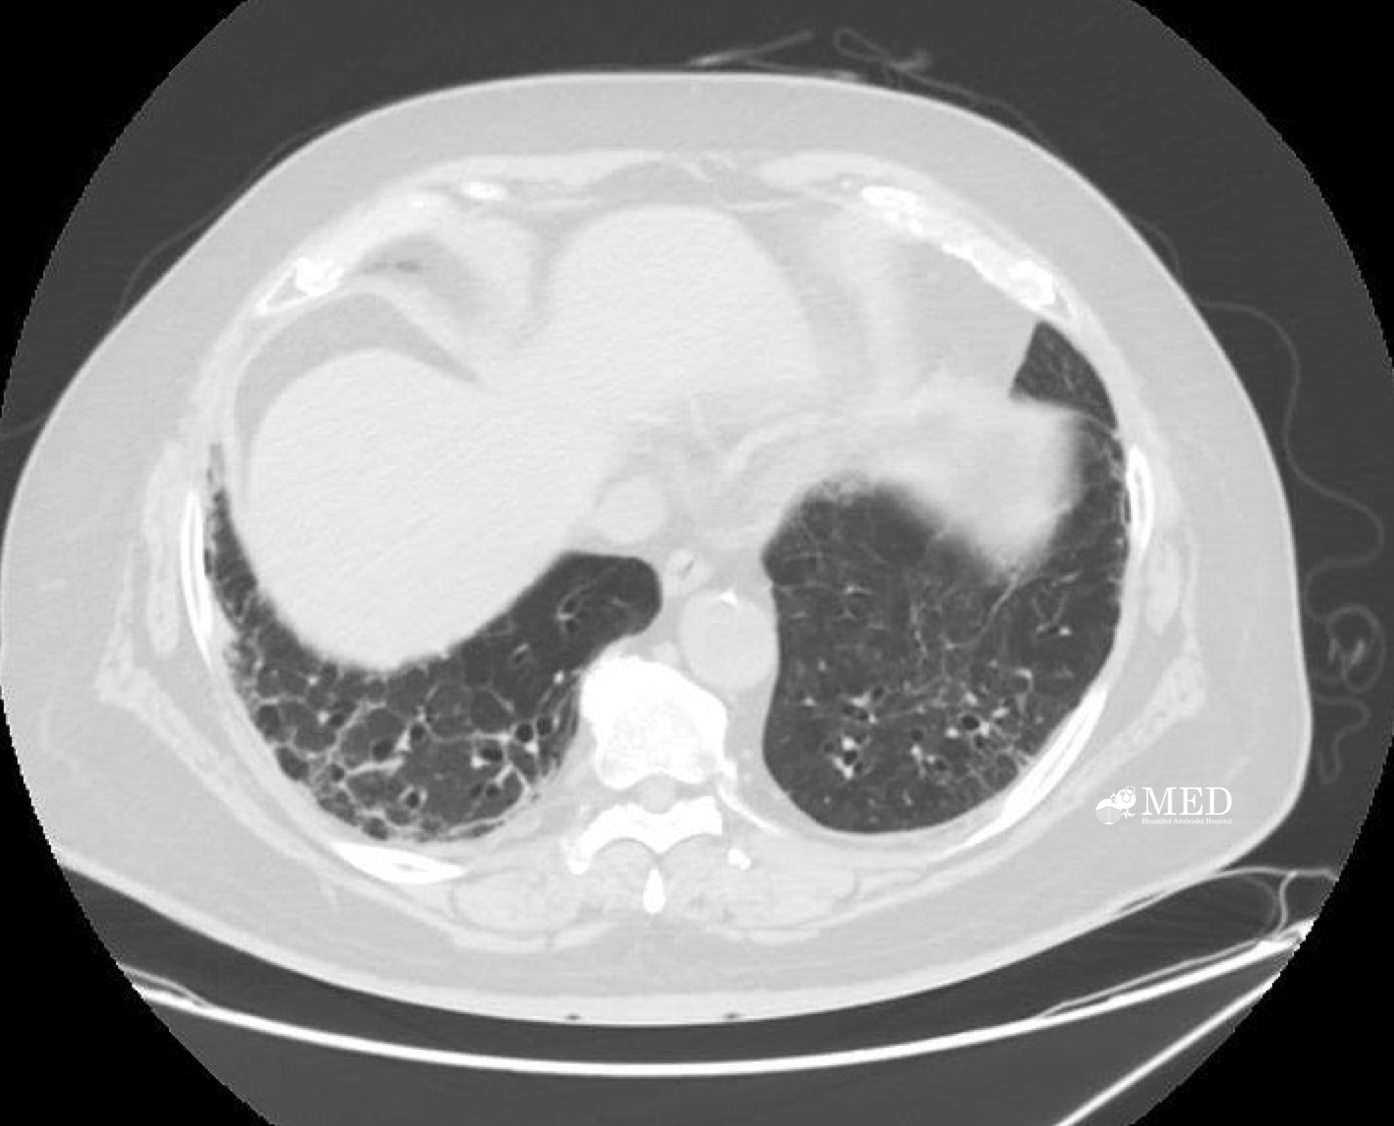

The high-resolution computed tomography (HRCT) scan was not performed due to the inability to schedule it in a timely manner pre-operatively. CT scan of chest was performed (as shown below).

1. Describe abnormal findings of CT chest and give provisional diagnosis.